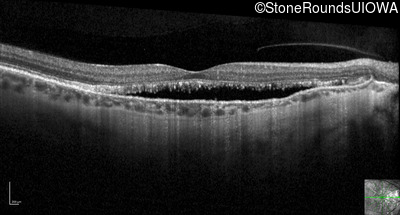

Optical Coherence Tomography - Right - 20/20 -3 sc

Exemplar / OCT Stack

OCT Stack